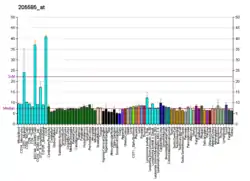

Hematological malignancies

The following table lists the more frequently occurring genes to which ETV6 fuses, the function of these genes, these genes' chromosomal locations, the notation designating the most common sites of the translocations of these fused genes, and the malignancies resulting from these translocations. These translocation mutations commonly occur in pluripotent hematopoietic stem cells that differentiate into various types of mature hematological cells. Consequently, a given mutation may lead to various types of hematological malignancies.[5][14] The table includes abbreviations for tyrosine kinase receptor (TK receptor), non-receptor tyrosine kinase (non-receptor TK), homeobox protein type of transcription factor (homeobox protein), acute lymphocytic leukemia (ALL), Philadelphia chromosome negative chronic myelogenous leukemia (Ph(-)CML), myelodysplastic syndrome (MDS), myeloproliferative neoplasm (MPN), and acute myeloid leukemia (AML). The presence of ETV6 gene mutations in myelodysplastic syndromes is associated with shortened survival.[15]